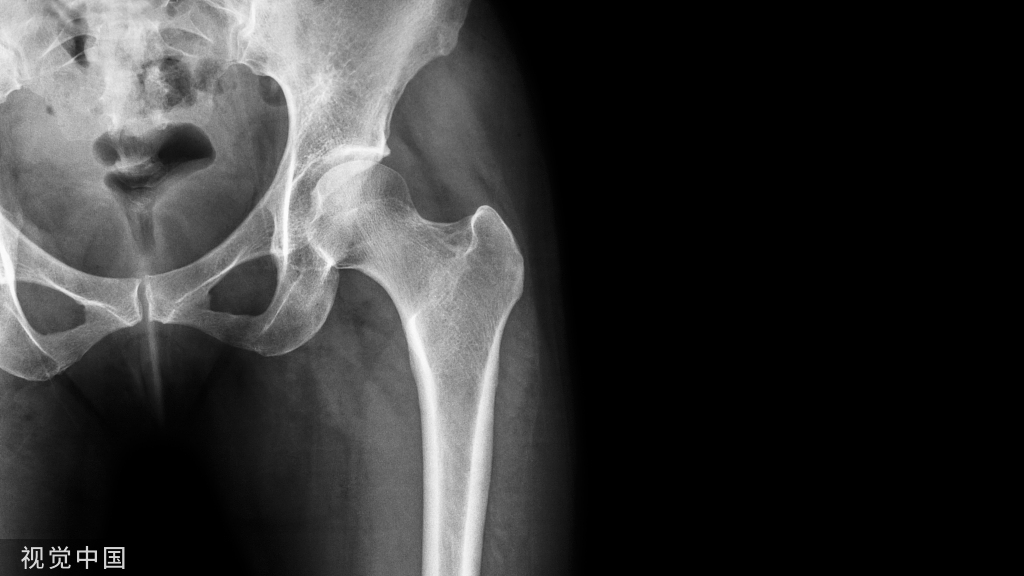

肩关节脱位(shoulder dislocation):很常见,约占全身关节脱位的50%。多发生在青壮年、男性较多。按肱骨头脱位的方向分为前脱位和后脱位等。肩关节前脱位者很多见,常因间接暴力所致。

肩关节前脱位(Anterior shoulder dislocation):肩关节脱位按肱骨头的位置分为前脱位和后脱位。肩关节前脱位者很多见,常因间接暴力所致,如跌倒时上肢外展外旋,暴力经过肱骨传导到肩关节,使肱骨头突破关节囊而发生脱位。

由于暴力的大小、力作用的方向以及肌肉的牵拉,前脱位时,肱骨头可能位于锁骨下、喙突下、肩前方及关节盂下。